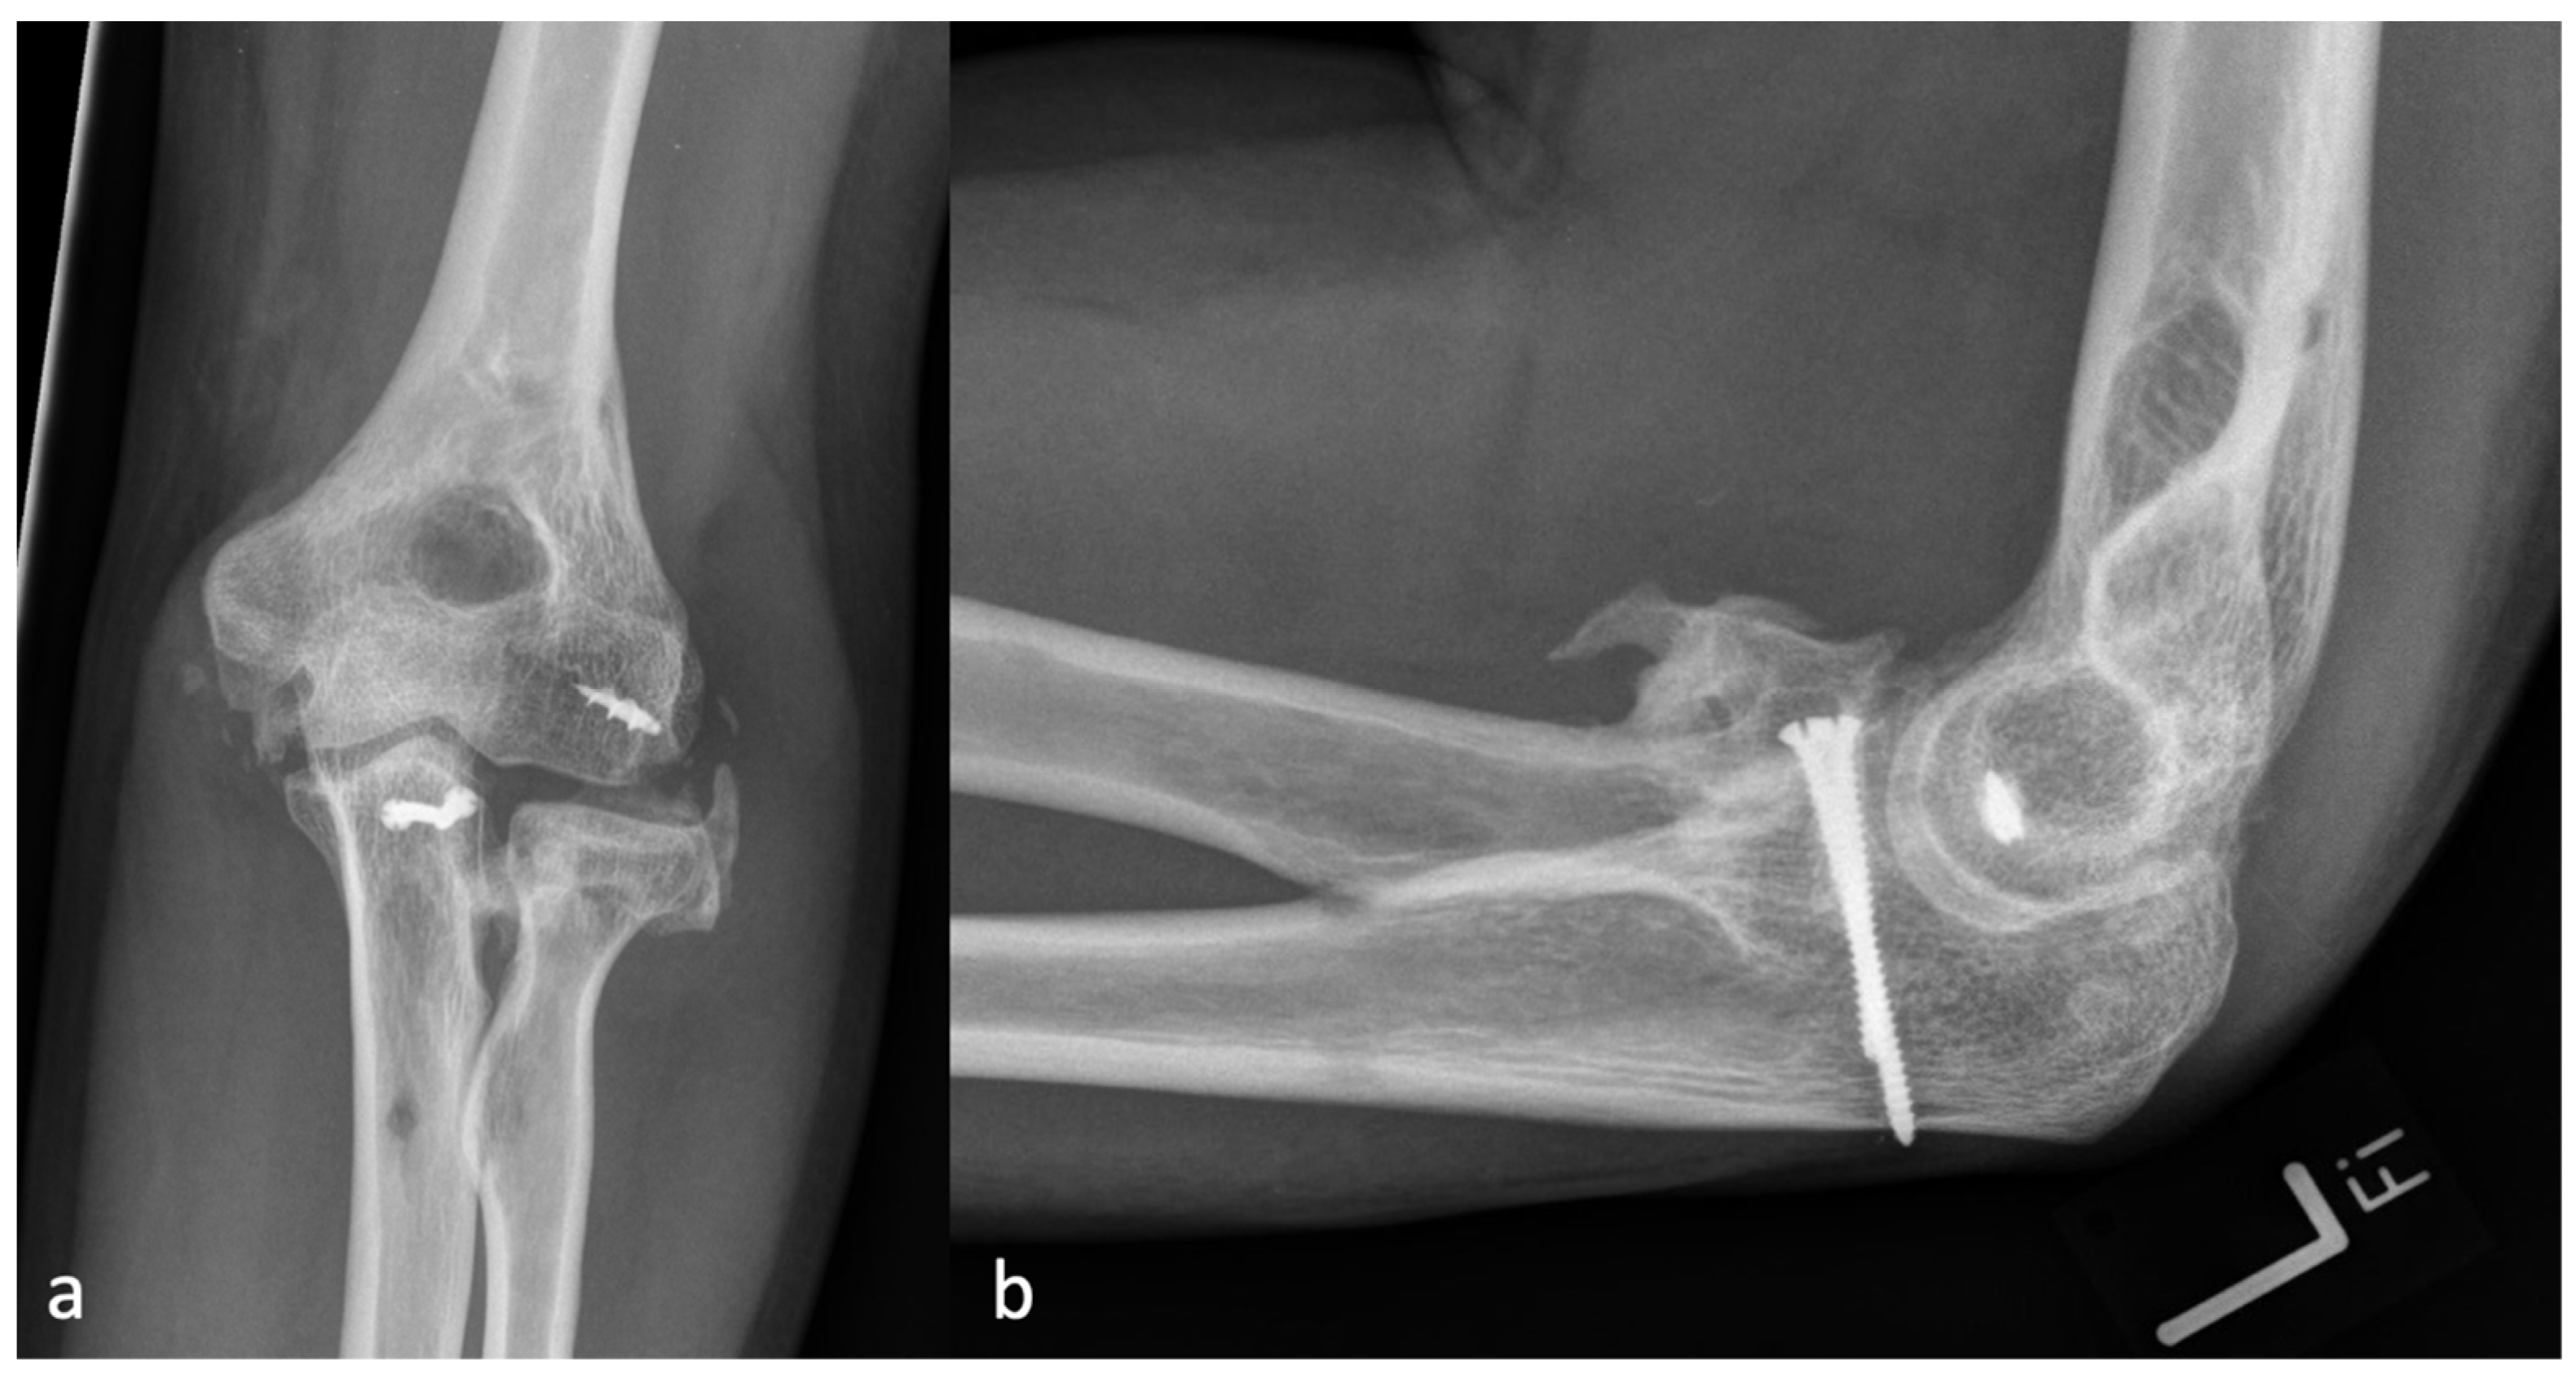

Figure 2.

(a) The AP and (b) the lateral X-ray with a radial HO smaller than the diameter of the radial head, which represents an HO 1 r.